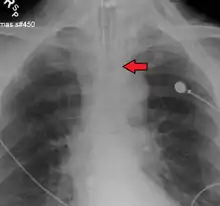

Ideally, at least one of the methods utilized for confirming tracheal tube placement will be a measuring instrument. Waveform capnography has emerged as the gold standard for the confirmation of tube placement within the trachea. Other methods relying on instruments include the use of a colorimetric end-tidal carbon dioxide detector, a self-inflating esophageal bulb, or an esophageal detection device.[36] The distal tip of a properly positioned tracheal tube will be located in the mid-trachea, roughly 2 cm (1 in) above the bifurcation of the carina; this can be confirmed by chest x-ray. If it is inserted too far into the trachea (beyond the carina), the tip of the tracheal tube is likely to be within the right main bronchus—a situation often referred to as a "right mainstem intubation". In this situation, the left lung may be unable to participate in ventilation, which can lead to decreased oxygen content due to ventilation/perfusion mismatch.[37]